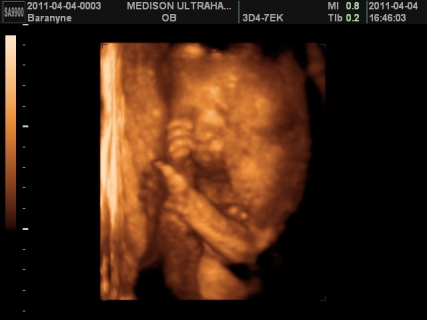

gyerek témában is helyretettem magam, ennek is tök egyszerű oka van, FÉLEK TŐLE. ezen nem változtat az idő, ha 1 év mulva mennék ,akkor is félnék tőle. sajnos nekem nem életem legszebb élménye volt a várandóság, én tényleg terhességként éltem meg. egyszerűen annyi a szabadságomnak, mert szinte mindenről le kell mondanom, bár remélem most nem így lesz meg. ámulva hallgatom, akinek a legszebb élmény a várandóság volt. valamilyen szinten nekem is, de csak mikor kiderült ,hogy sikerült és mikor megszületett boti, a többi rész kihagynám, mert nem tudtam önfeledten örülni sem az első szívhangnak, sem az első uh-nak, mert mindig bennem volt a félsz. ezt talán legjobban bibó értheti meg. viszont nagyon nagyon szeretnék egy kismanót, de egyszerűen nem tudom elképzelni, hogy hogy fogom tudni boti mellett megoldani. anyuékhoz sem passzolhatom le mindig botit, ha mondjuk fáradt leszek, vagy isten ne adja vérzek. mi lesz vele? na ezen ráérek agyalni, de már nem sokáig, mert kb 3 hét és visszaülti. bár tudnék felhőtlenül örülni, de a félelmemet nem tudom leküzdeni. alig várom ,hogy jöjjön a kisboti